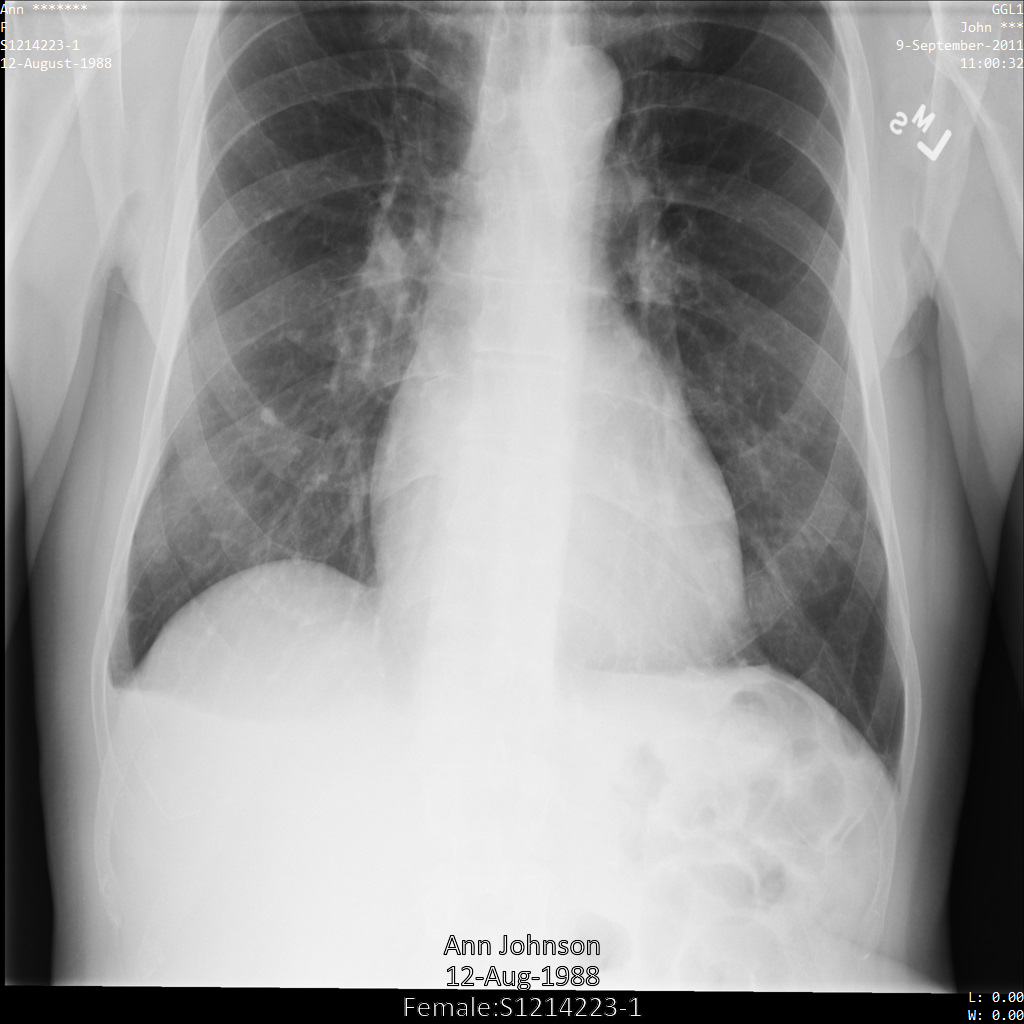

Después de enviar la imagen a la API Cloud Healthcare, la imagen aparece de la siguiente manera. Aunque se han ocultado los metadatos que aparecen en las esquinas superiores de la imagen, la información médica protegida (PHI) que aparece en la parte inferior de la imagen no se ha modificado. Para quitar el texto insertado, consulta Ocultar el texto insertado de las imágenes.

Después de enviar la imagen a la API Cloud Healthcare, la imagen aparece de la siguiente manera. De las etiquetas proporcionadas en removelist, solo se elimina PatientBirthDate

de la imagen, ya que es la única etiqueta de removelist que

corresponde a metadatos visibles en la imagen.

Aunque el PatientBirthDate de la esquina superior de la imagen se ha ocultado de acuerdo con la configuración de la lista de elementos que se deben eliminar, la información sanitaria personal (ISP) grabada en la parte inferior de la imagen permanece. Para quitar el texto insertado, consulta Ocultar el texto insertado de las imágenes.

Después de enviar la imagen a la API Cloud Healthcare mediante el perfil de filtro de etiquetas ATTRIBUTE_CONFIDENTIALITY_BASIC_PROFILE, la imagen aparece de la siguiente manera. Aunque los metadatos que se muestran en las esquinas superiores de la imagen se han ocultado, la información personal protegida que aparece en la parte inferior de la imagen sigue ahí.

Para eliminar también el texto insertado, consulta el artículo Ocultar el texto insertado de las imágenes.